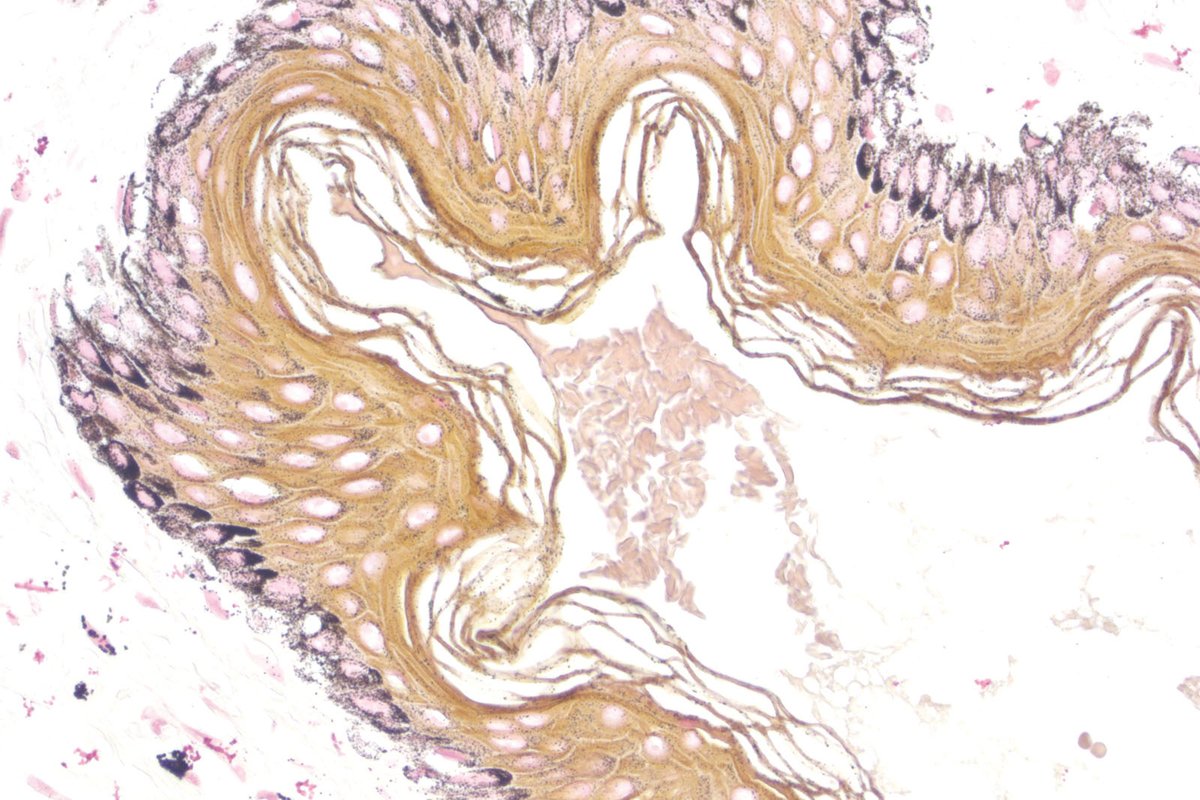

📌 Warthin Starry

يتم استخدامها للتشخيص باكتيريا

Spirochaete and H pylori

والنتيجة عندنا تظهر عندنا بالاسود للأثنين

اما بالنسبة الأنسجة يكون لونها اصفر الى البني